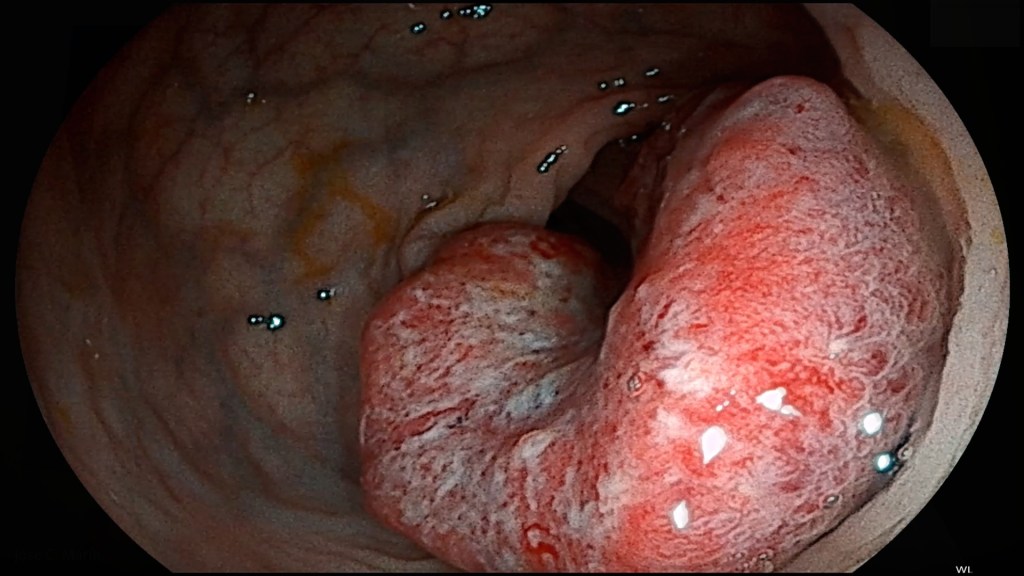

Con el cribado de cáncer de colon pretendemos reducir la incidencia de este tipo de tumores en el conjunto de la población: descubrir cánceres en estadios precoces o detectar las lesiones precursoras del cáncer, adenomas (tumores no cancerosos), que son los pólipos en el colon.

Este es otro mito recurrente que preocupa y genera dudas razonables a l@s pacientes, que tienen mucho miedo a una perforación en el tubo digestivo… empero, no existe dato o estudio clínico alguno que apoye esta afirmación.

Cada vez que se quita un pólipo se forma una cicatriz en la mucosa intestinal, como cuando te haces una herida en la piel. Las cicatrices, por regla general, son tejidos más duros y resistentes.

Y aunque no fuera ese el caso, asumiendo que la pared del colon es muy delgada en algunas zonas (menos de 5 mm de espesor), estamos ante un órgano muy largo con una superficie lo suficientemente extensa para que no se debilite al extirpar múltiples pólipos.

Recalco, hasta la fecha no existe evidencia médico-científica que nos alerte de que varias colonoscopias consecutivas, extirpando un buen número de pólipos, aumente el riesgo de perforación en el tracto inferior del aparato digestivo.